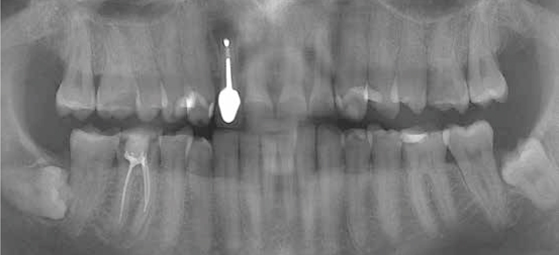

Afb. 8

OPT

Röntgenonderzoek

Röntgenologisch onderzoek laat meerdere problemen zien. Onder andere een forse zwarting apicaal van element 12 met het beeld passend bij periapicale problematiek en een verleden van apicale chirurgie (afbeelding 8-12 ).